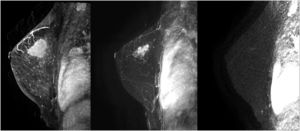

The studies were performed in decubitus prone position, using a 3.0 Tesla device (General Electric Medical Systems®), sequences enhanced in T1 and T2 in sagittal plane followed by diffusion sequence in axial plane. These were followed by the dynamic study with 3D T1-enhanced gradient echo sequences (Fast Spoiled Gradient Echo:FSPGR) with fat suppression in the bilateral sagittal plane. Images were obtained before and after intravenous injection of gadopentate dimeglumine, using an automatic injector (Magnevist®), delivering 0.1 mmol/l per kg weight, followed by a 20 ml bolus of saline solution to flush the intravenous cannula, at an injection rate of 3 ml/s. Slice thicknesses of 2.5–3 mm were used, depending on breast size, with an in-plane resolution of 0.8*0.6 mm. Temporal resolution of 60 s was achieved per 3D sequence. A total of seven 3D sequences were acquired, the first without contrast medium and the following 6 after administration of the medium. The total duration for the dynamic study was 7 min (Fig. 1). Finally, after the dynamic study, late enhancement was performed in the axial plane (3D VIBRANT) with fat suppression, achieving a resolution of 0.5*0.5 mm, acquiring a slice thickness of 2 mm for subsequent study. Examinations were interpreted by radiologists with more than 10 years of experience in breast MRI. The response was analyzed using late enhancement sequences, obtaining images at 2, 6 and 10 min. (Fig. 2). This protocol is used just when evaluating patients treated with neoadjuvant chemotherapy.

Second, and from our perspective, the most important finding in our study was the results obtained using Spearman rho analysis for cases with incomplete pCR. These presented a lineal curve, reaching a statistically significant correlation between residual tumor sizes in the pre-surgical MRI and in the surgical specimen (Fig. 3). Therefore, in our experience and in patients with partial pathologic response, late enhancement sequences MRI accurately predicts the residual tumor size in breast cancer patients, following chemotherapy. This may be an important factor to avoid positive margins in patients undergoing conservative surgery. In fact, we only observed a 2.2% of affected margins in this series. As we can see in Fig. 2 compared to Fig. 1 (both from the same patient), the fact of obtaining late enhancement sequences allows to avoid a false assessment of complete response by image if only the dynamic study had been taken into account, visualizing gadolinium enhancement in the images obtained at 6 and 10 min.

Prospective randomized studies comparing the use of late enhancement sequences with conventional imaging acquisition protocols in MRI (Fig. 1) are needed to conclusively establish their potential usefulness; and possibly, in a near future, radiologic evaluation of malignant breast neoplasms by MRI will be implemented by machine and deep learning methods, which are already starting to be used in other imaging techniques.28